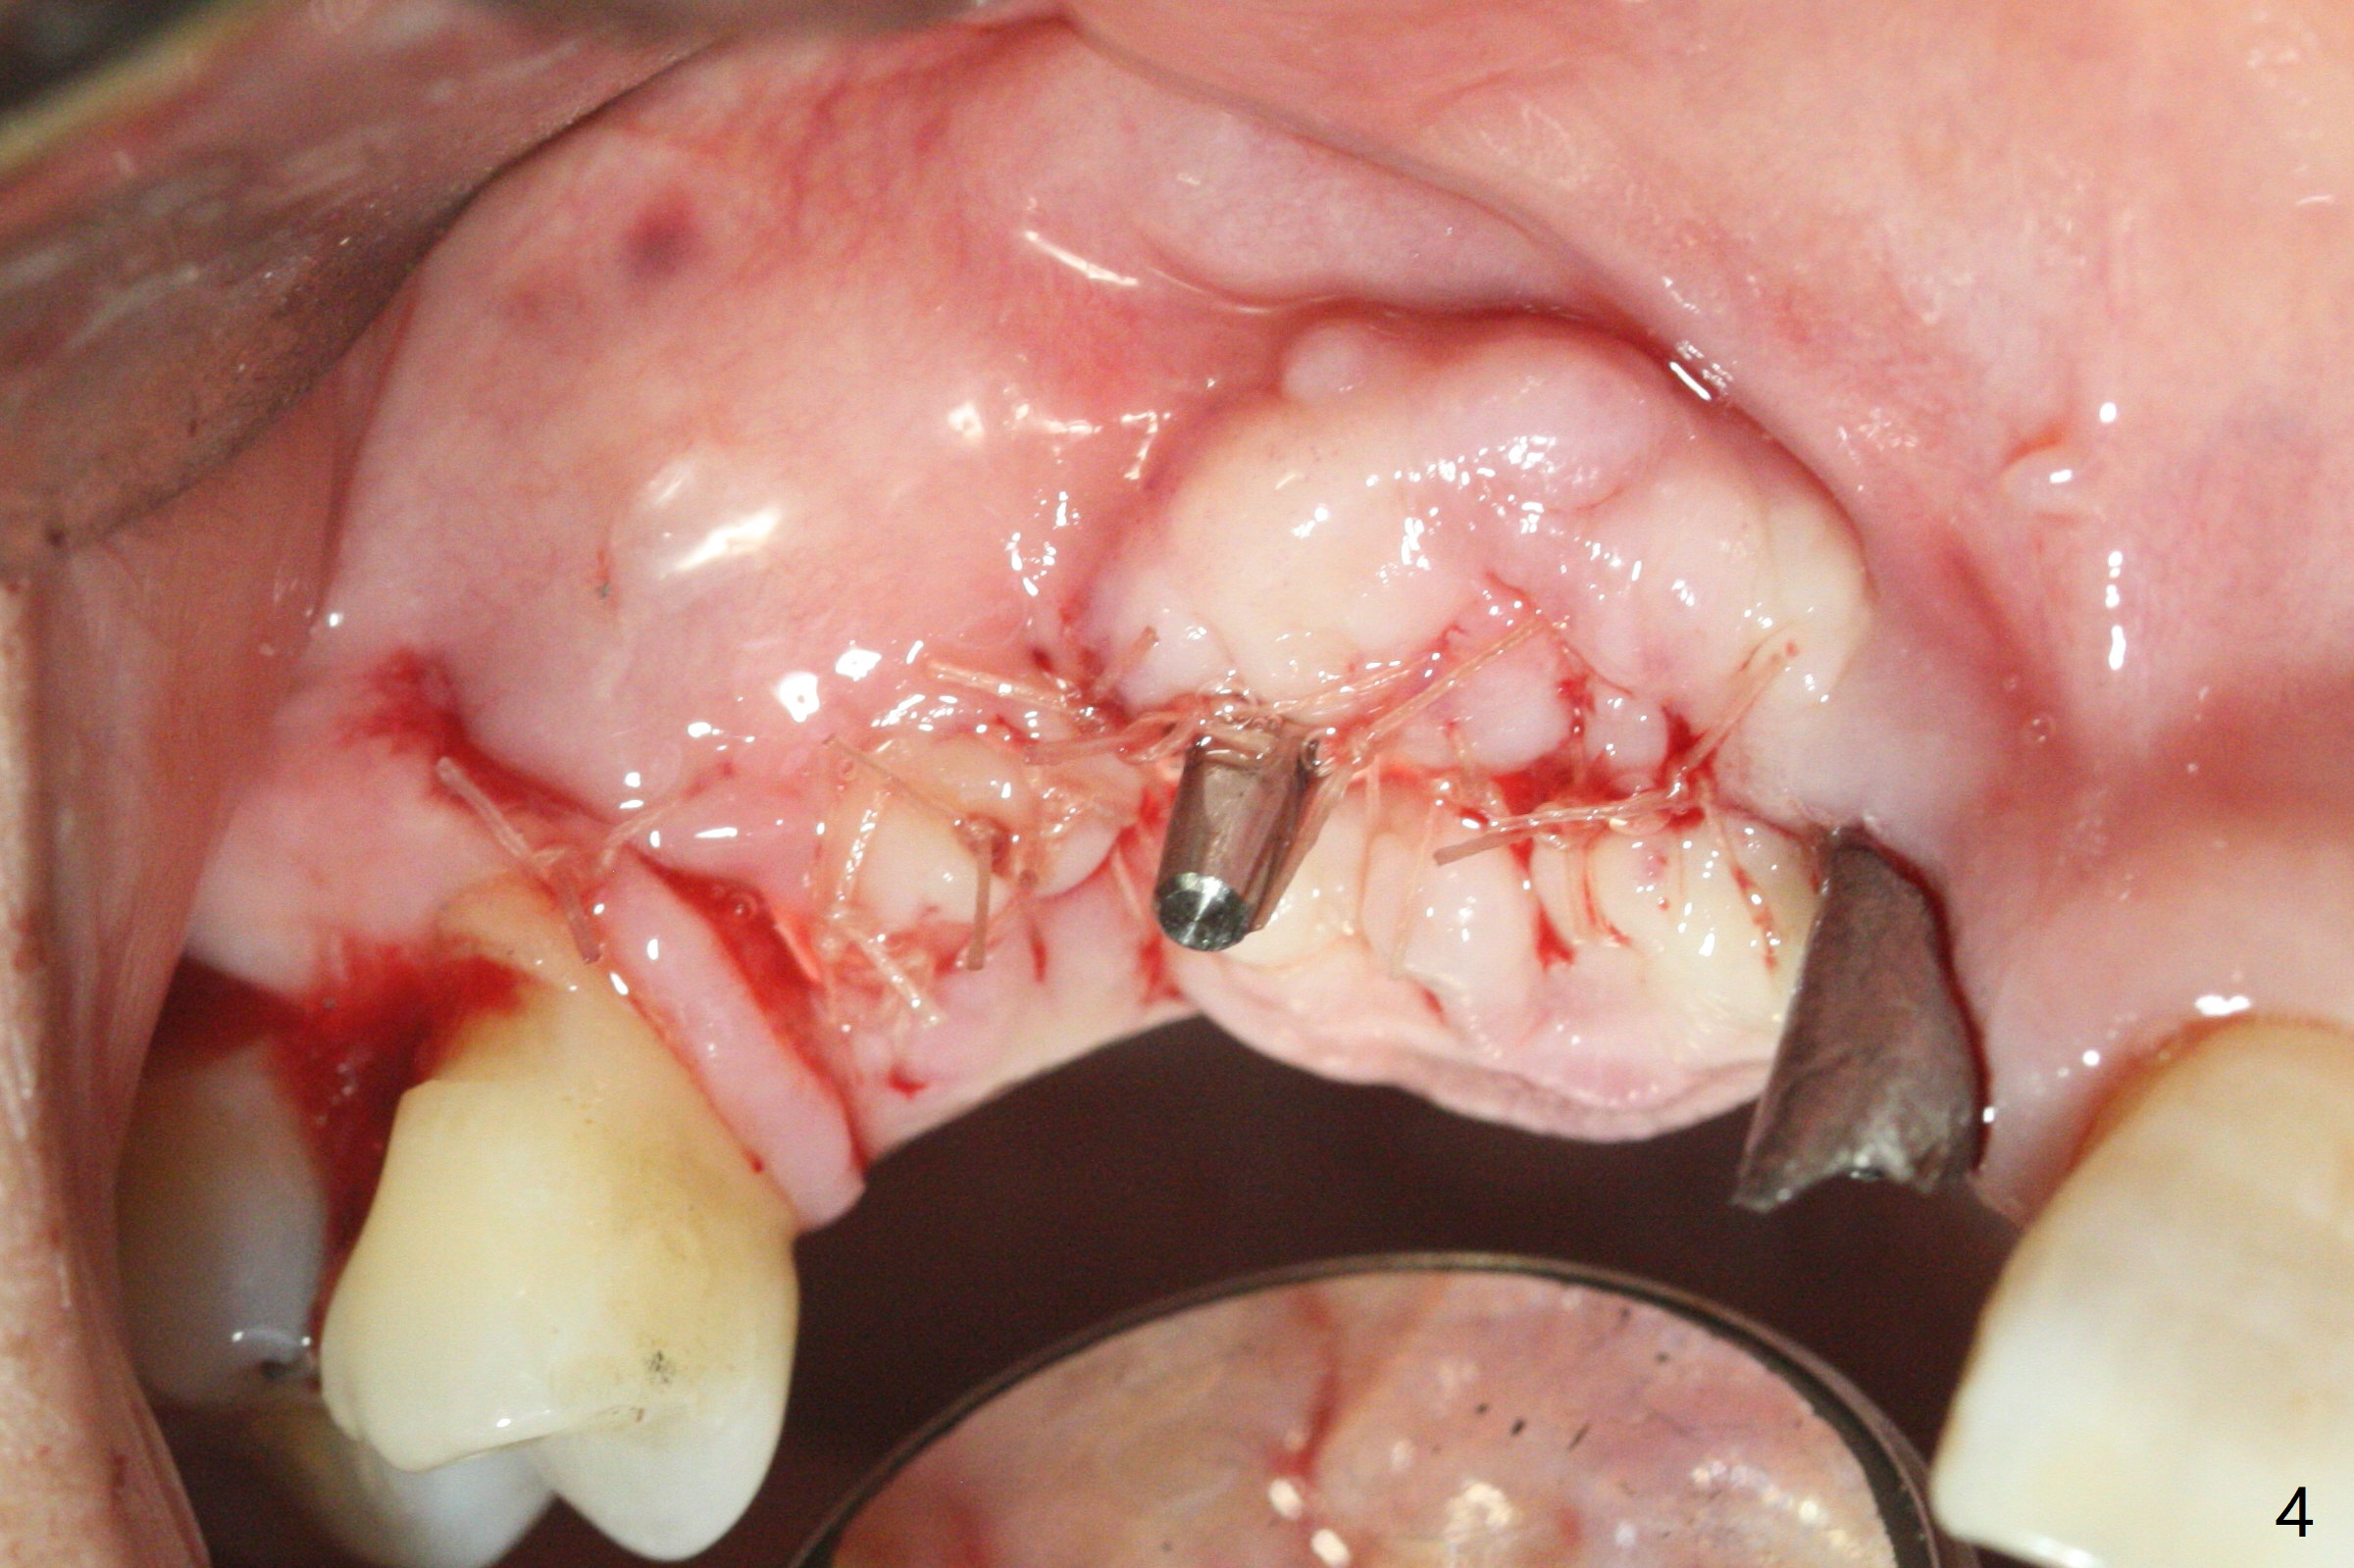

5,7号牙两段式植体种植后螺纹暴露,植骨后4-5个月,准备5号牙uncover,病人主诉7号牙出血,切开后发现两个植体螺纹仍旧暴露(图一,二),看样子保留不住,而6号牙位牙槽嵴不宽,准备植入2x8.5毫米一段式植体,结果骨质高度允许植入10毫米植体(图二,三),然后使用外科钻头和环形刀(trephine bur)取出两段式植体,填入粘性骨粉(图三:*),覆盖PRF和不可吸收膜,4-0 PGA缝合(图四),最后牙周敷料。5,7牙位愈合也可以植入一段式植体,让植体之间距离大些,植骨后颊侧腭侧宽度也可能不足。